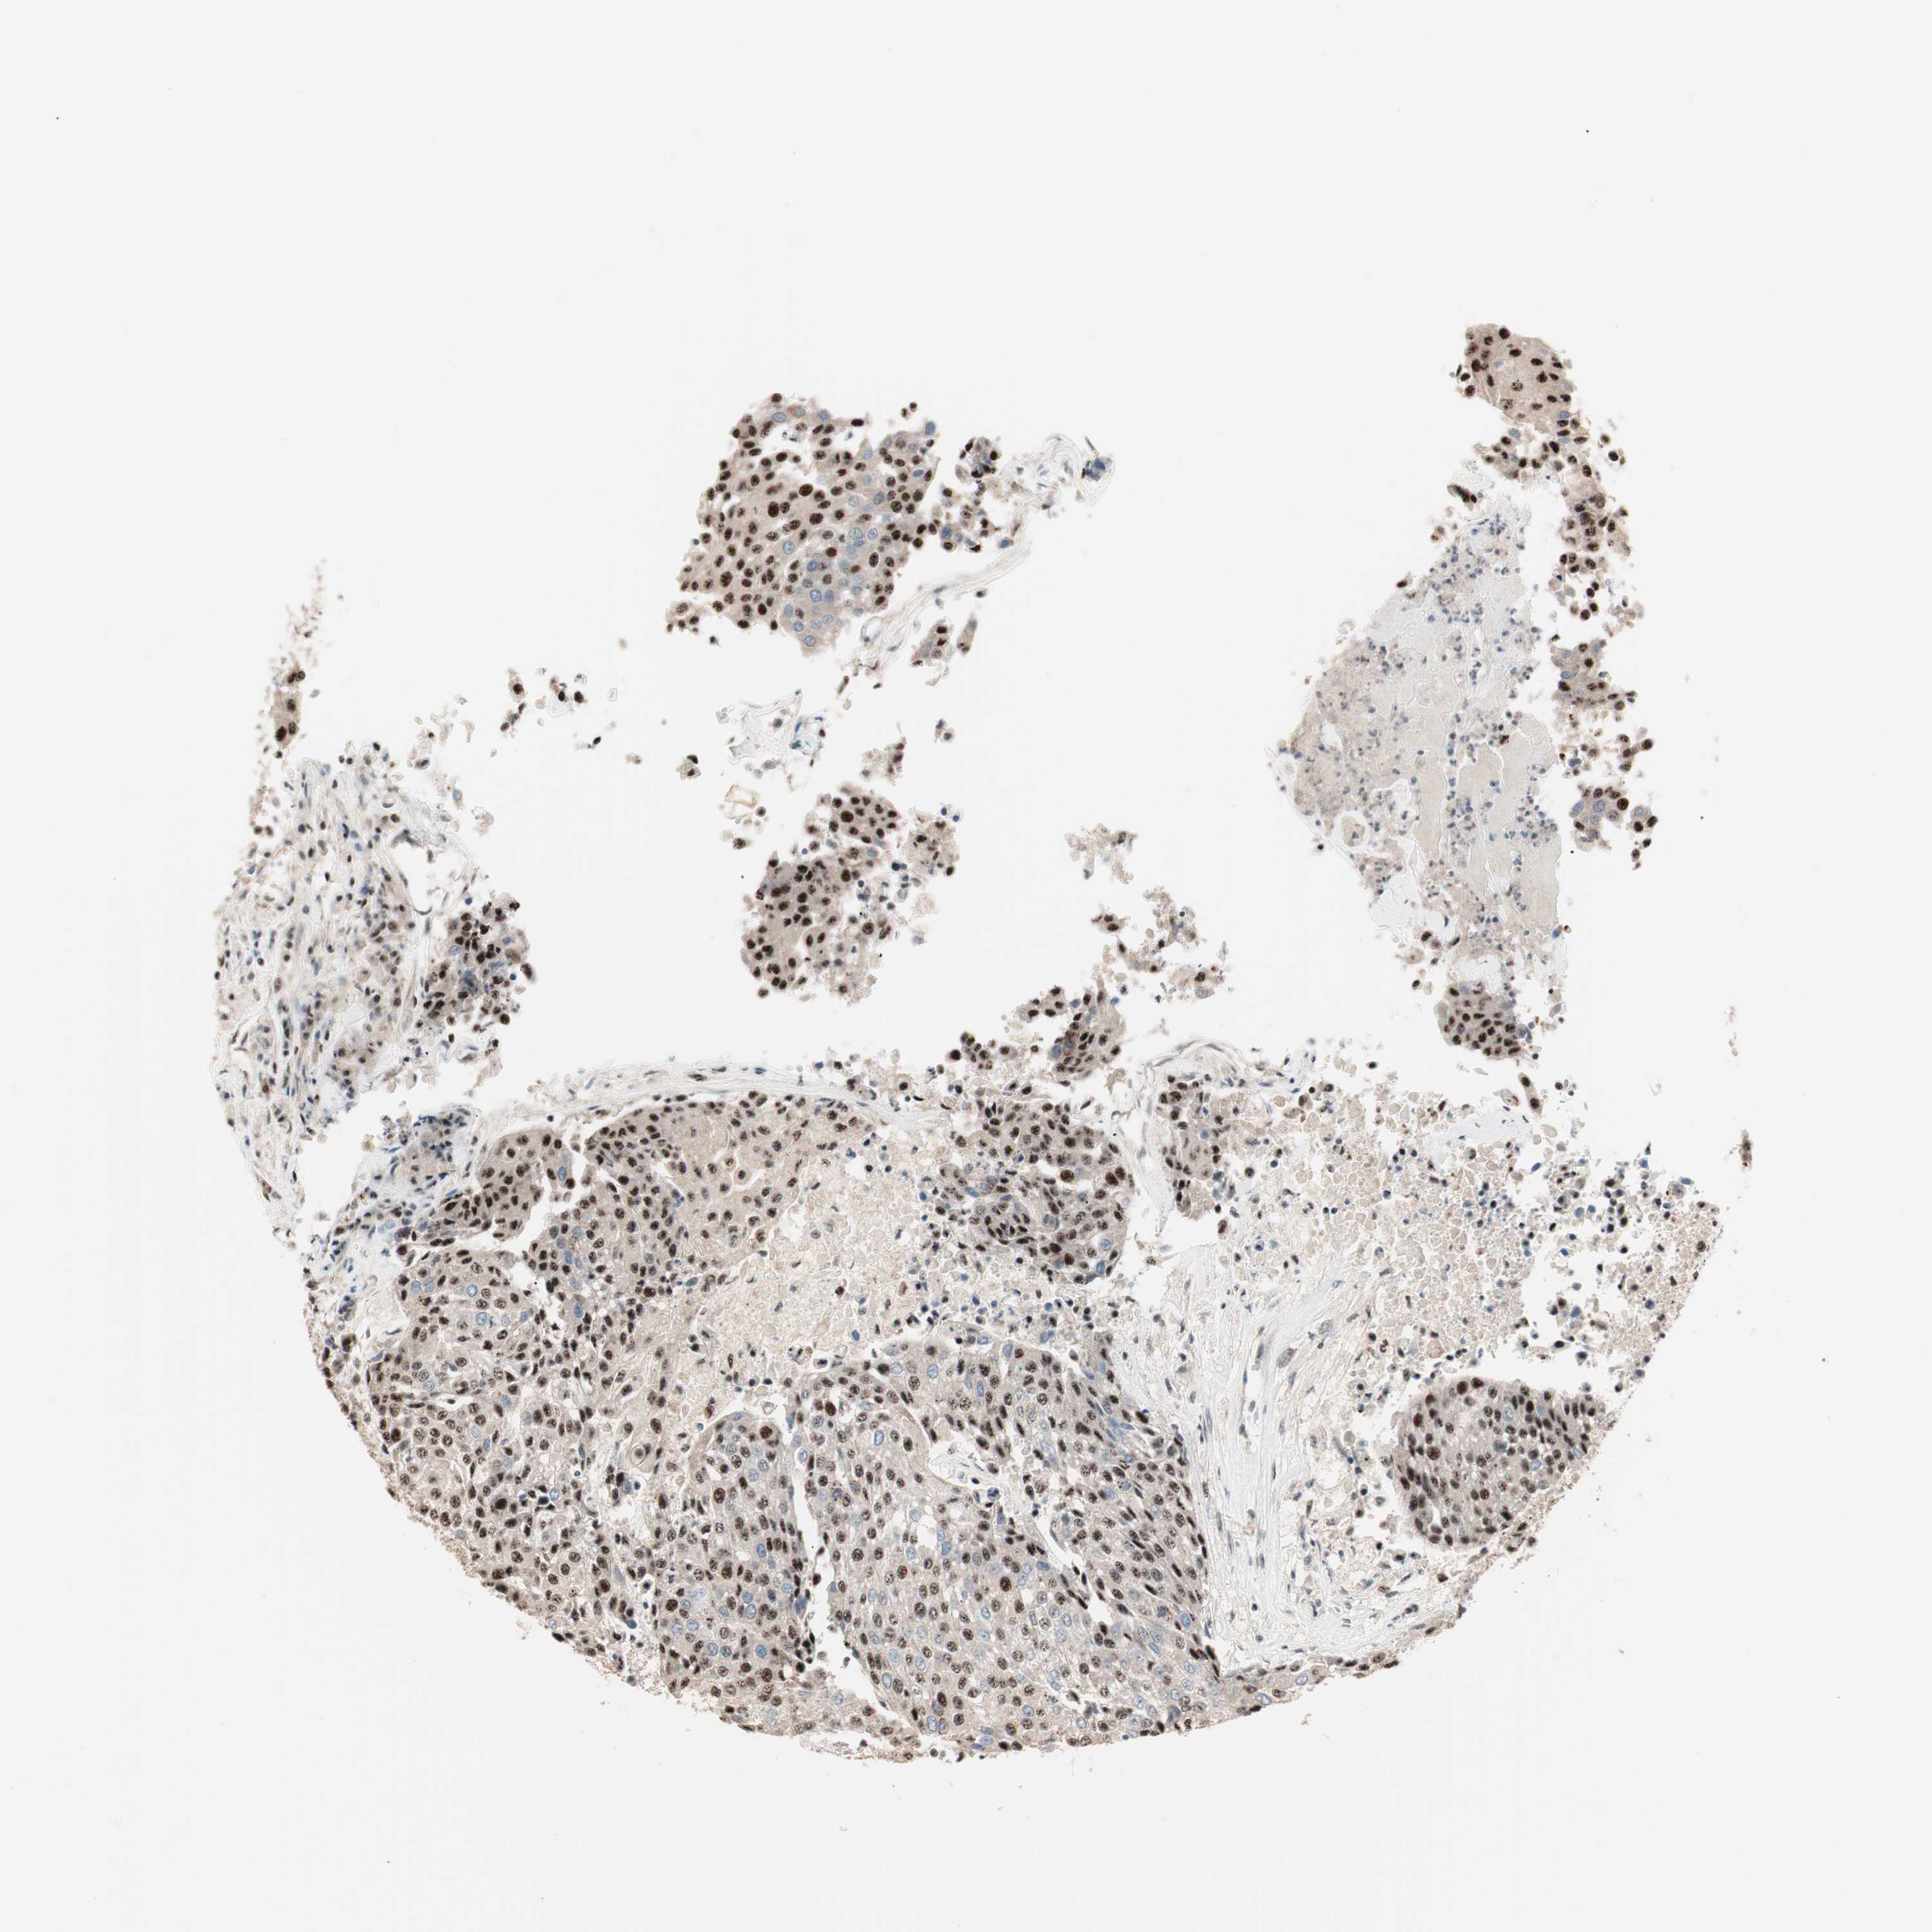

UROTHELIAL CANCER - Protein expressioni

A mouse-over function shows sample information and annotation data. Click on an image to view it in a full screen mode. Samples can be filtered based on level of antibody staining by selecting one or several of the following categories: high, medium, low and not detected. The assay and annotation is described here.

Note that samples used for immunohistochemistry by the Human Protein Atlas do not correspond to samples in the TCGA dataset.

Antibody stainingi

Antibody staining in the annotated cell types in the current human tissue is reported as not detected, low, medium, or high, based on conventional immunohistochemistry profiling in selected tissues. This score is based on the combination of the staining intensity and fraction of stained cells.

Each image is clickable and will lead to virtual microscopy that enables deeper exploration of all samples and also displays staining intensity scores, fraction scores and subcellular localization as well as patient and tissue information for each sample.

Antibody HPA005455

Antibody HPA017067

Urothelial carcinoma, Low grade

Urothelial carcinoma, High grade